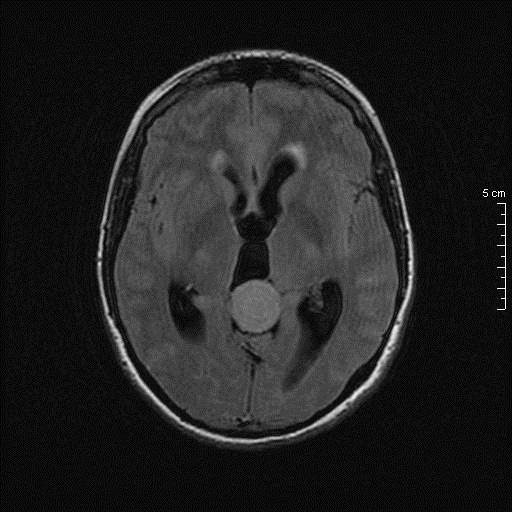

Η ασθενής κινητοποιήθηκε πλήρως την πρώτη μετεγχειρητική ημέρα χωρίς νέο εστιακό νευρολογικό έλλειμμα και έλαβε εξιτήριο την επομένη.

Μετεγχειρητικός απεικονιστικός έλεγχος